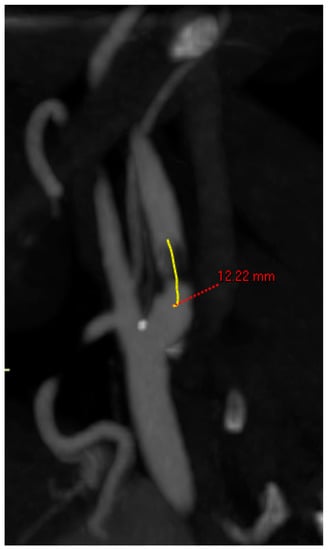

- Length of lesion: centerline measurement in mm of the entire length of the atherosclerotic lesion (Figure 2);

Figure 2. Centerline measurement of the length of the lesion.